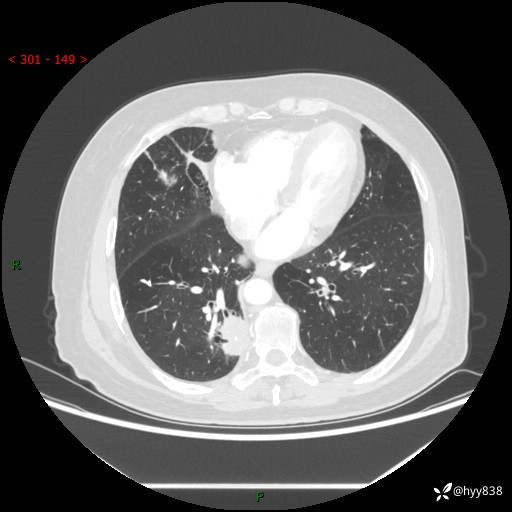

增强动脉期+静脉期

两期CT值:55Hu 53hu